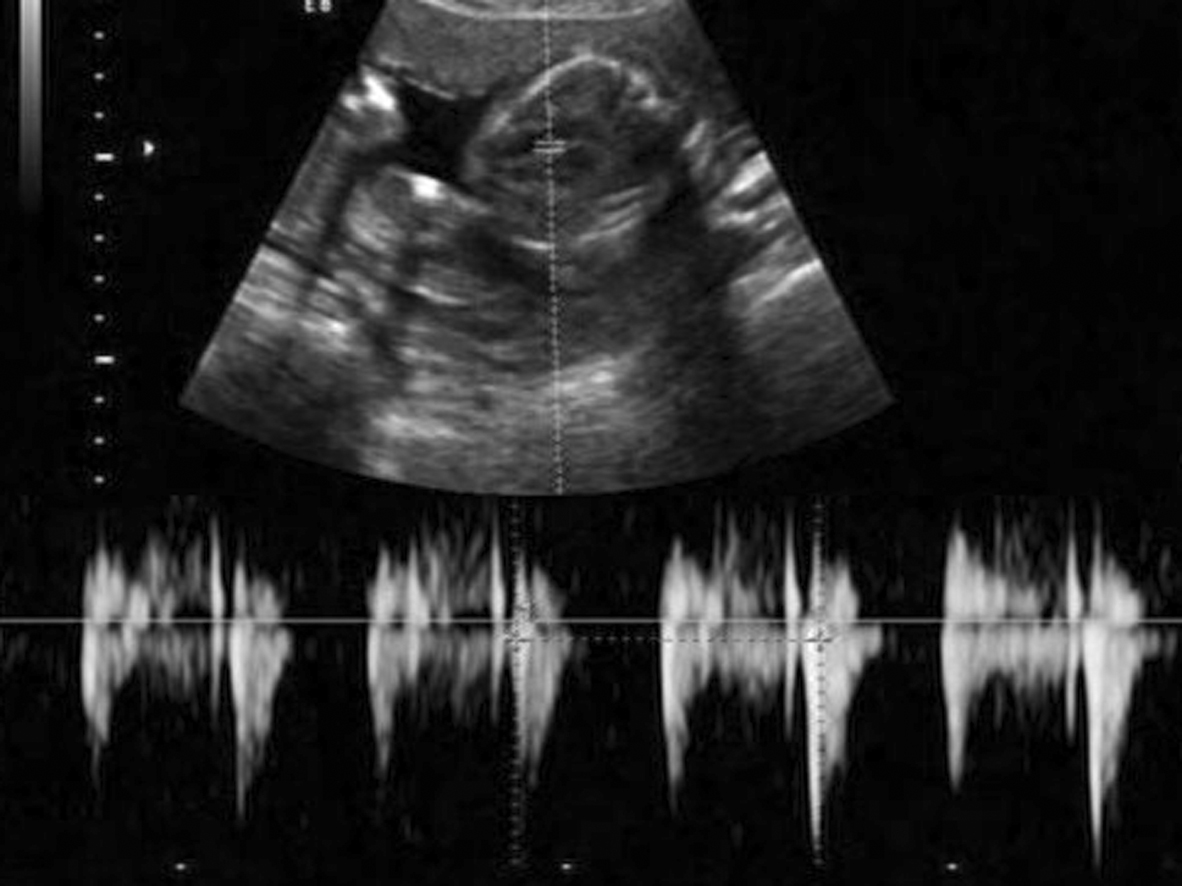

超声显像检查是观察胎动的敏感方法。实时超声检查可以在第7孕周以后显示胎儿活动。早期的胎动显示为较小的肢体摆动或颤动;第15周以后已经可以区分呃逆,呼吸样运动,四肢活动,翻转/旋转、头部活动,下颌运动,吸吮和吞咽,打呵欠,伸展等(图3);高分辨率的仪器可以在第18周显示胎儿眼球的活动。

图3胎儿张*活口**动声像图A:箭头示胎儿闭口 B:箭头示胎儿口部张开